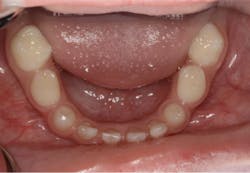

Upon clinical and radiographic examination, the patient presented with multiple missing permanent teeth (figures 3, 4a, and 4b). Tooth No. 8 was malpositioned and slightly mobile. Her mandibular dentition was stable and intact, although mostly deciduous (figure 5). Upon further questioning, I learned that her brother had a similar condition. Taking into consideration the patient’s physical appearance and the genetic similarity to her brother, I discussed with her parents the need to obtain a medical diagnosis through genetic testing.